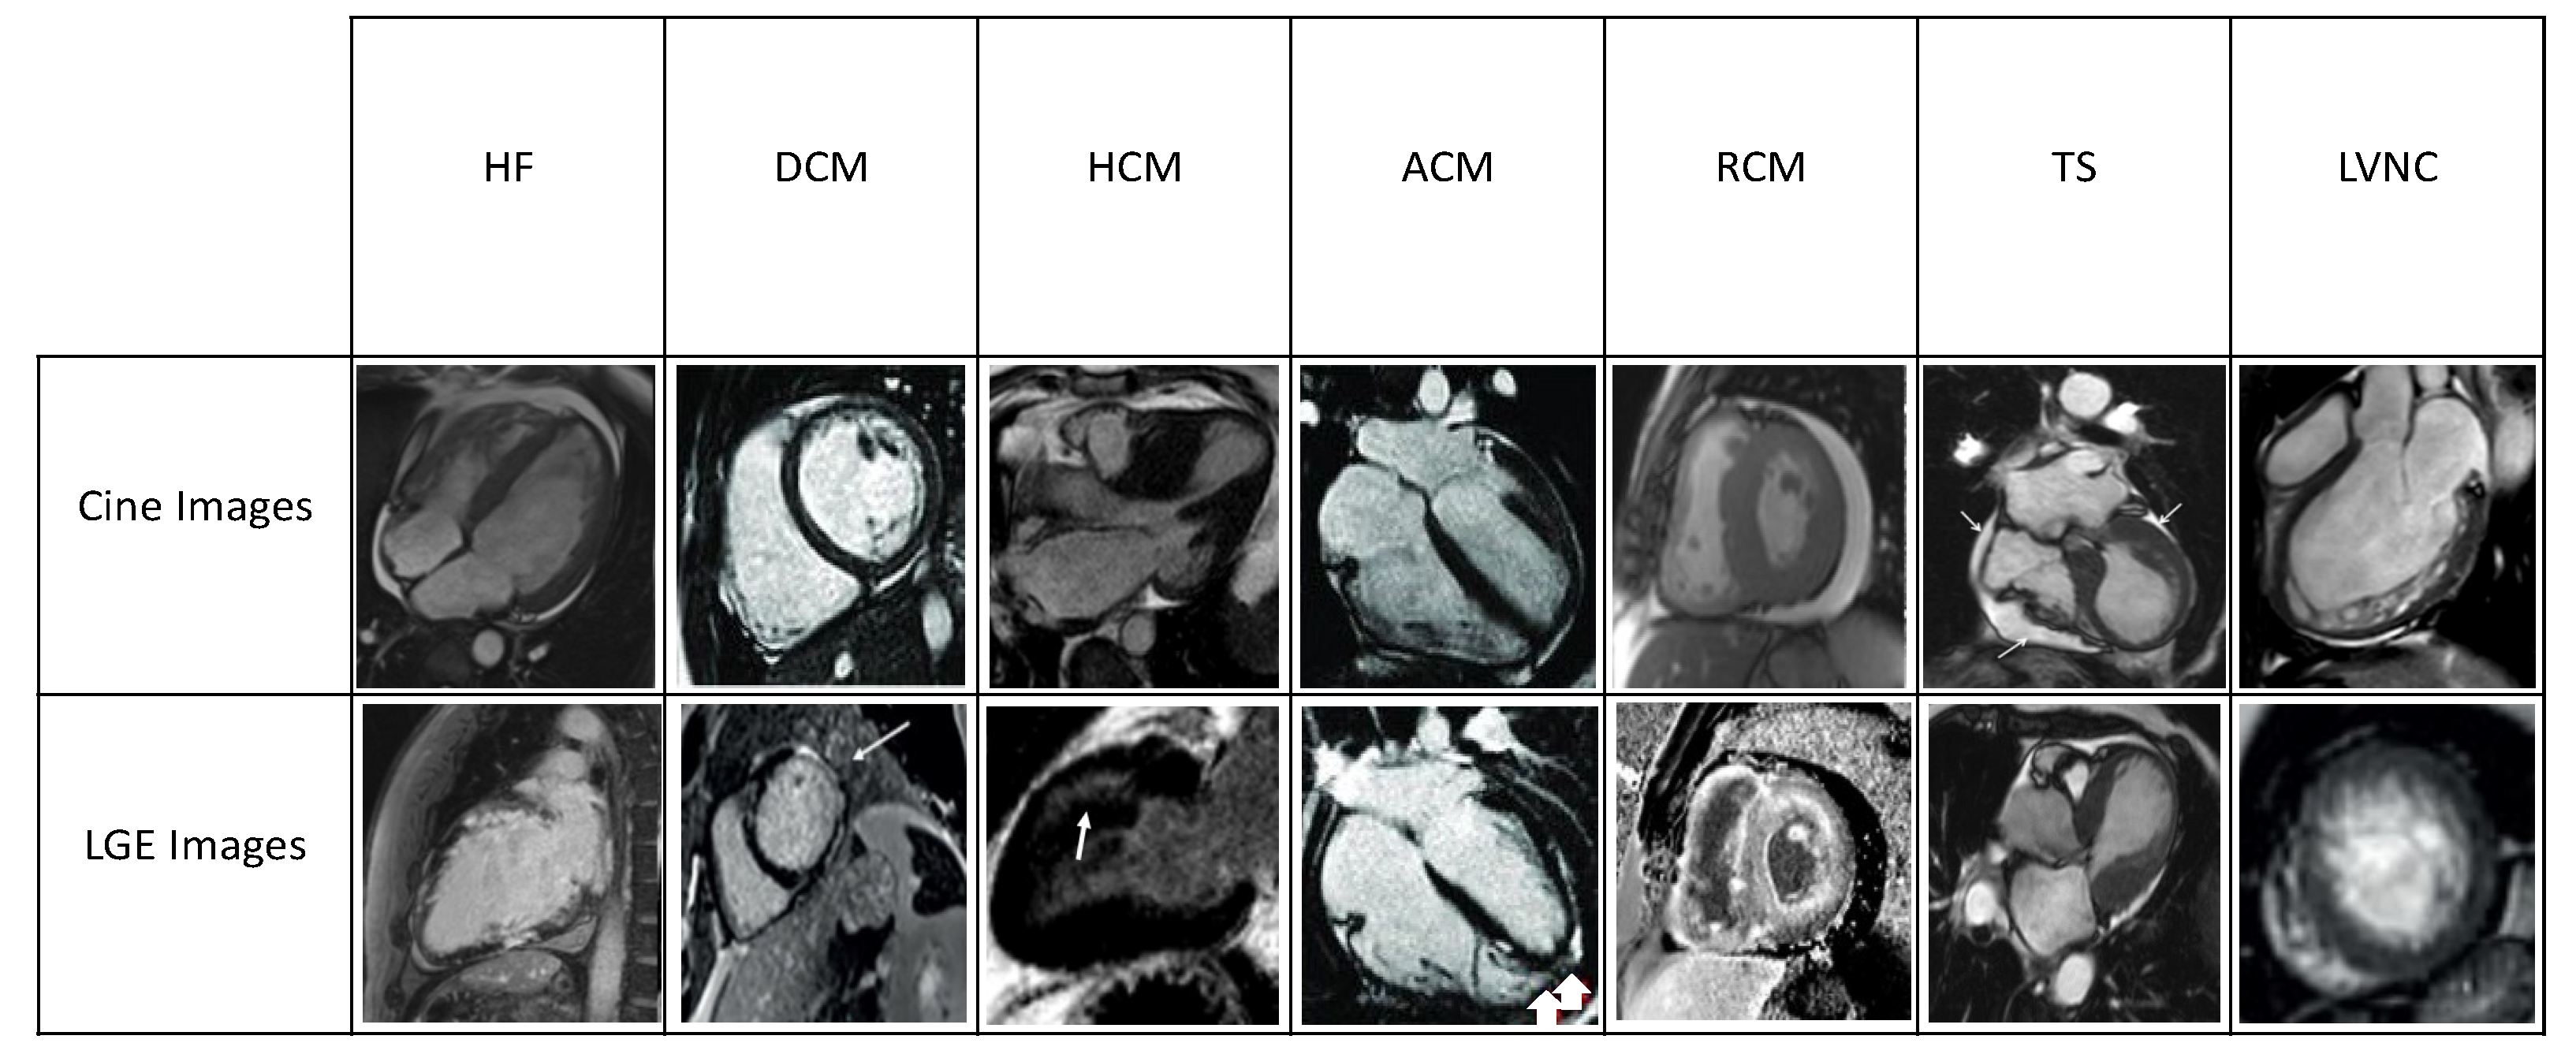

2. CMR in HF

3. CMR in Dilated Cardiomyopathy

4. CMR in Hypertrophic Cardiomyopathy

5. CMR in Arrhythmogenic Cardiomyopathy

6. CMR in Restrictive Cardiomyopathy

7. CMR in in Left Ventricular Noncompaction

8. CMR in Takotsubo Syndrome